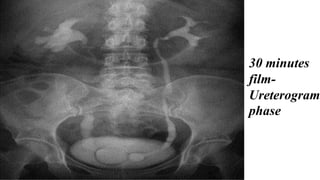

• Dilation of Left

Renal Pelvis and

Calyces Above the

Obstructing

Calculus

• Dilation ofLeft Renal Pelvis and Calyces Above the Obstructing Calculus